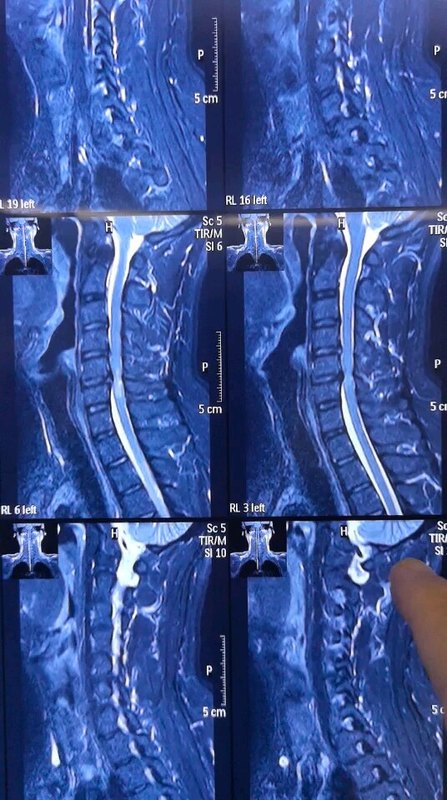

許多患者在檢查頸椎的時候,發(fā)現(xiàn)自己的報告單上寫著“頸椎間盤突出、脊髓變性”等字樣,這個時候醫(yī)生就會告知情況嚴重,需要手術!這就讓不少患者非常糾結(jié),真的就必須手術嗎?而在網(wǎng)上一查,都說脊髓變性了肯定要手術,而且術后可能還恢復不好。這是真的嗎?最近,宣武醫(yī)院王作偉主任就接診了一位62歲的女性患者。她在1年前就出現(xiàn)了右側(cè)上肢疼痛,雙下肢的酸麻、行走不穩(wěn)的情況,去了當?shù)蒯t(yī)院檢查后發(fā)現(xiàn)是脊髓型頸椎病,并告知脊髓變性了,需要盡快手術。當時她覺得自己的癥狀不是特別嚴重,就沒有立即手術,服用了一些藥物,做了保守治療。但是今年她的癥狀越來越重,行走困難,要人扶著才能走,上肢也疼痛劇烈,什么活兒也干不了。這次,家里人就很重視了,去了不少醫(yī)院,都建議她盡快手術,有的醫(yī)生還說脊髓變性了,脊髓有了一定損傷,術后可能就恢復不好了。這讓她們一家很擔心,現(xiàn)在已經(jīng)不是手術不手術的問題,而是做了手術能不能恢復的問題了。為了進一步治療,他們決定去北京大醫(yī)院再看看,最后找到了王主任。脊髓型頸椎病出現(xiàn)的脊髓變性是怎么回事?脊髓型頸椎病是頸椎病眾多類型中最危險的一型,它之所以這么危險,就是因為壓迫到脊髓。那報告當中的脊髓變性又是怎么回事?簡單來說,就是脊髓受壓久了,脊髓缺血了,這種情況持續(xù)時間長了就產(chǎn)生了脊髓變性。如果再不盡快處理,繼續(xù)發(fā)展下去就會有脊髓壞死的可能,到那個時候患者就會癱瘓。所以,一旦確診為脊髓型頸椎病后,都是建議盡快手術,避免病情向最嚴重的情況(癱瘓)繼續(xù)發(fā)展。脊髓變性在頸椎的核磁共振片子上顯示很明確,椎管內(nèi)正常的脊髓是暗黑色的一條,而脊髓變性的地方顏色呈現(xiàn)變白、變淺。就像這位患者的片子,在頸5-6、頸6-7處的椎間盤有突出,而且嚴重壓迫到了后面的脊髓,尤其是頸5-6水平處的脊髓顯示變淺,提示有脊髓變性。術前影像學資料:脊髓變性了再做手術后還能完全恢復嗎?這還是需要根據(jù)患者術前的具體情況而定,如果患者術前脊髓變性很輕、時間短,術后的各項功能還是可以恢復的;但如果患者術前脊髓受壓時間特別久,變性也很嚴重,術后的癥狀就會恢復得很慢,甚至一部分功能出現(xiàn)不可逆的損傷,這時就不能完全恢復了。但相比完全癱瘓來說,盡早手術給脊髓減壓還是非常有必要的。這位患者在了解后就馬上同意了手術,王主任根據(jù)她的具體情況為她定制了微創(chuàng)的頸前路手術,并在其后為她成功完成手術。手術中在保護周圍神經(jīng)、脊髓、血管等組織的情況下,將兩個節(jié)段的椎間盤突出切除,給脊髓進行了徹底減壓,并進行內(nèi)固定建立頸椎的穩(wěn)定性。術后,她右上肢疼痛癥狀得到很快緩解,下肢麻木也得到了一定改善,在術后三天,她已經(jīng)可以自己獨立行走了,效果很好。術后影像學資料:其實,脊髓型頸椎病只要確診了,都是需要手術的,而且早做手術要比晚做的效果好很多,有時甚至是天壤之別,所以還是建議大家能早做就早做,不要拖到后面脊髓變性得很嚴重了再做。